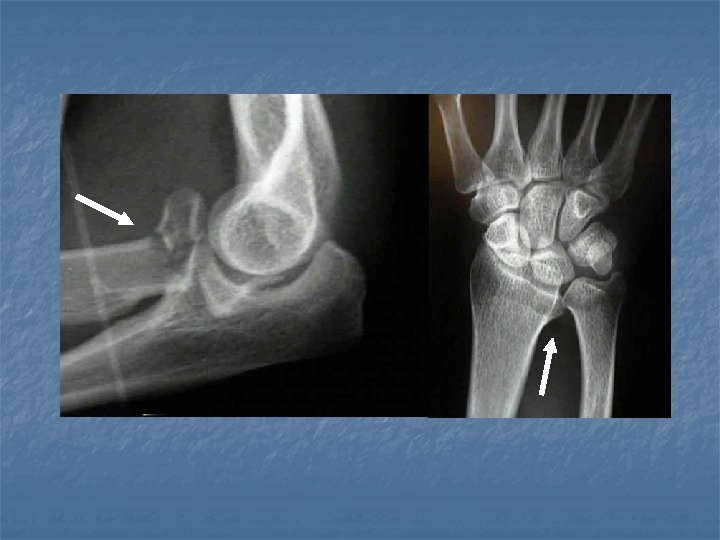

Essex-Lopresti Fracture-Dislocation Complex type injury which comprises 1. Comminuted fracture of the radial head and neck +/- distal extension. 2. Tear of the interosseous membrane. 3. Dislocation in the distal radioulnar joint.

Galeazzi Fracture–Dislocation This injury type comprises: 1. 2. Fracture of the distal third of the radius, Dislocation in the distal radioulnar joint.